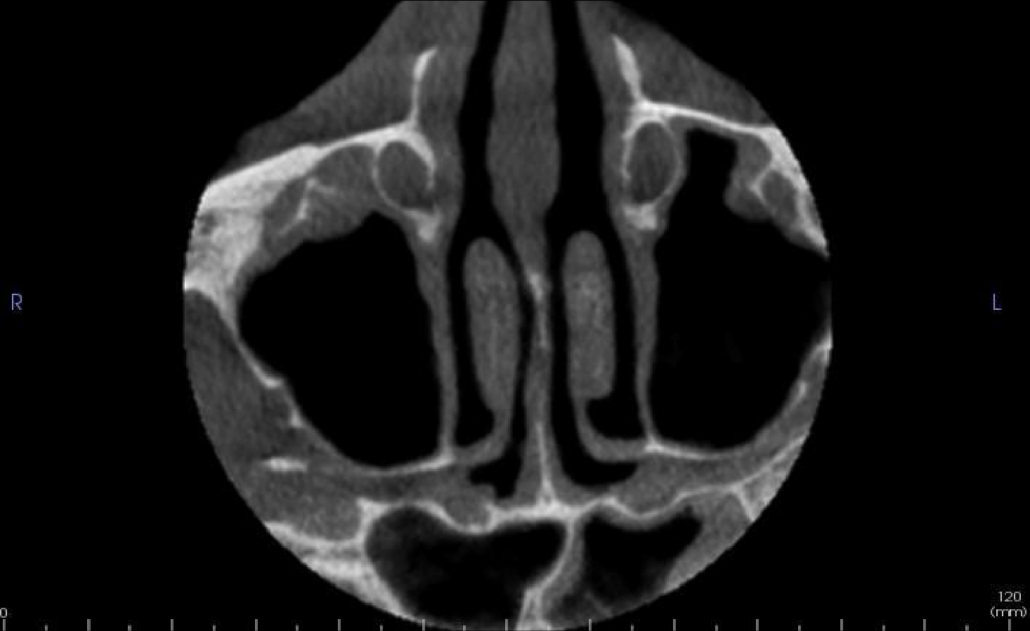

Both maxillary and left sphenoid sinuses have mild generalised thickening of the mucosal linings. There is no expansion or bony erosion of the sinus walls.

Axial and coronal slices showing mucosal lining thickening of the left sphenoid sinus